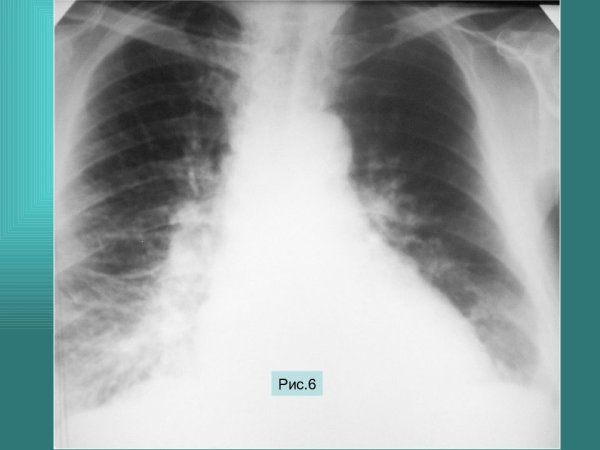

Усиление лёгочного рисунка на рентгенограмме